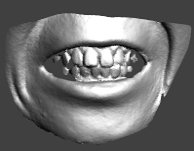

使用事例: 整形美容外科

美容整形を希望する患者にとって自分自身が、術後どのような姿に変わるのか大いに気になり、心配するところです。患者は術後の様子を他患者の例で紹介されることがあると聞きますが、はやり自分がどのように変貌するか前もって確認したいところです。その場合、術後の自分を3Dで見ながら説明を受けると、どう変貌するか容易に理解できます。例えば、術後にどのぐらい鼻が高くなり、または しわが減るのか、あるいは二重まぶたや顎が横からどのように見られるのか、術前に確認できます。そのためには最初に術前の姿を3D計測し、このモデルを元に術後の姿を、担当医と相談しながら決めていくことができます。

術前の姿を高精度で3Dモデルを作る機器としては、ハンディ3Dスキャナーが最適です。ハンディ3Dスキャナーはレーザーとは異なり、写真撮影で三次元のモデルを作っていきます。そのため操作前のカリブレーションが不要で、またデータ合成用のマーカーも必要ありません。ちょうど「アイロンをかける」ようなイメージで、顔の周りを移動しながら計測していきます。顔の3Dモデルの作成時間は、計測も含めて約10分です。術後の姿を患者に前もって伝えることは、インフォームド・コンセントになります。